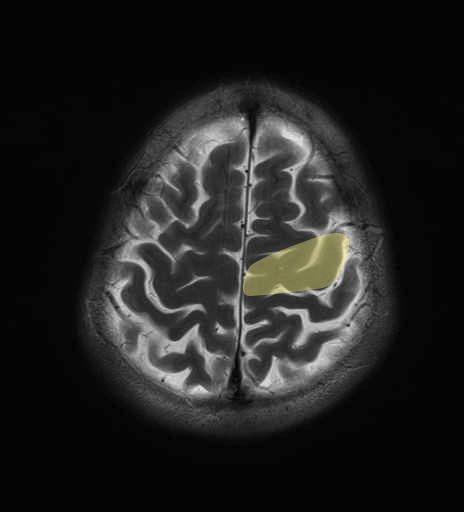

錐体路・皮質脊髄路のMRI画像解剖

運動系 錐体路系に色を付けました。

■皮質脊髄路(いわゆる錐体路):一次運動野から脊髄遠隔の下位運動ニューロン細胞体まで